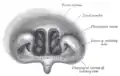

تیغه بینی

تیغه بینی گذرگاه هوای سمت چپ و راست بینی را از هم جدا میکند و آنها را تبدیل به دو حفره بینی میکند.

این تیغه در پشت استخوانی بوده ولی در قدام بینی ساختاری غضروفی دارد.استخوان خیش بخش پشتی زیرین، تیغه بینی را ایجاد میکند.